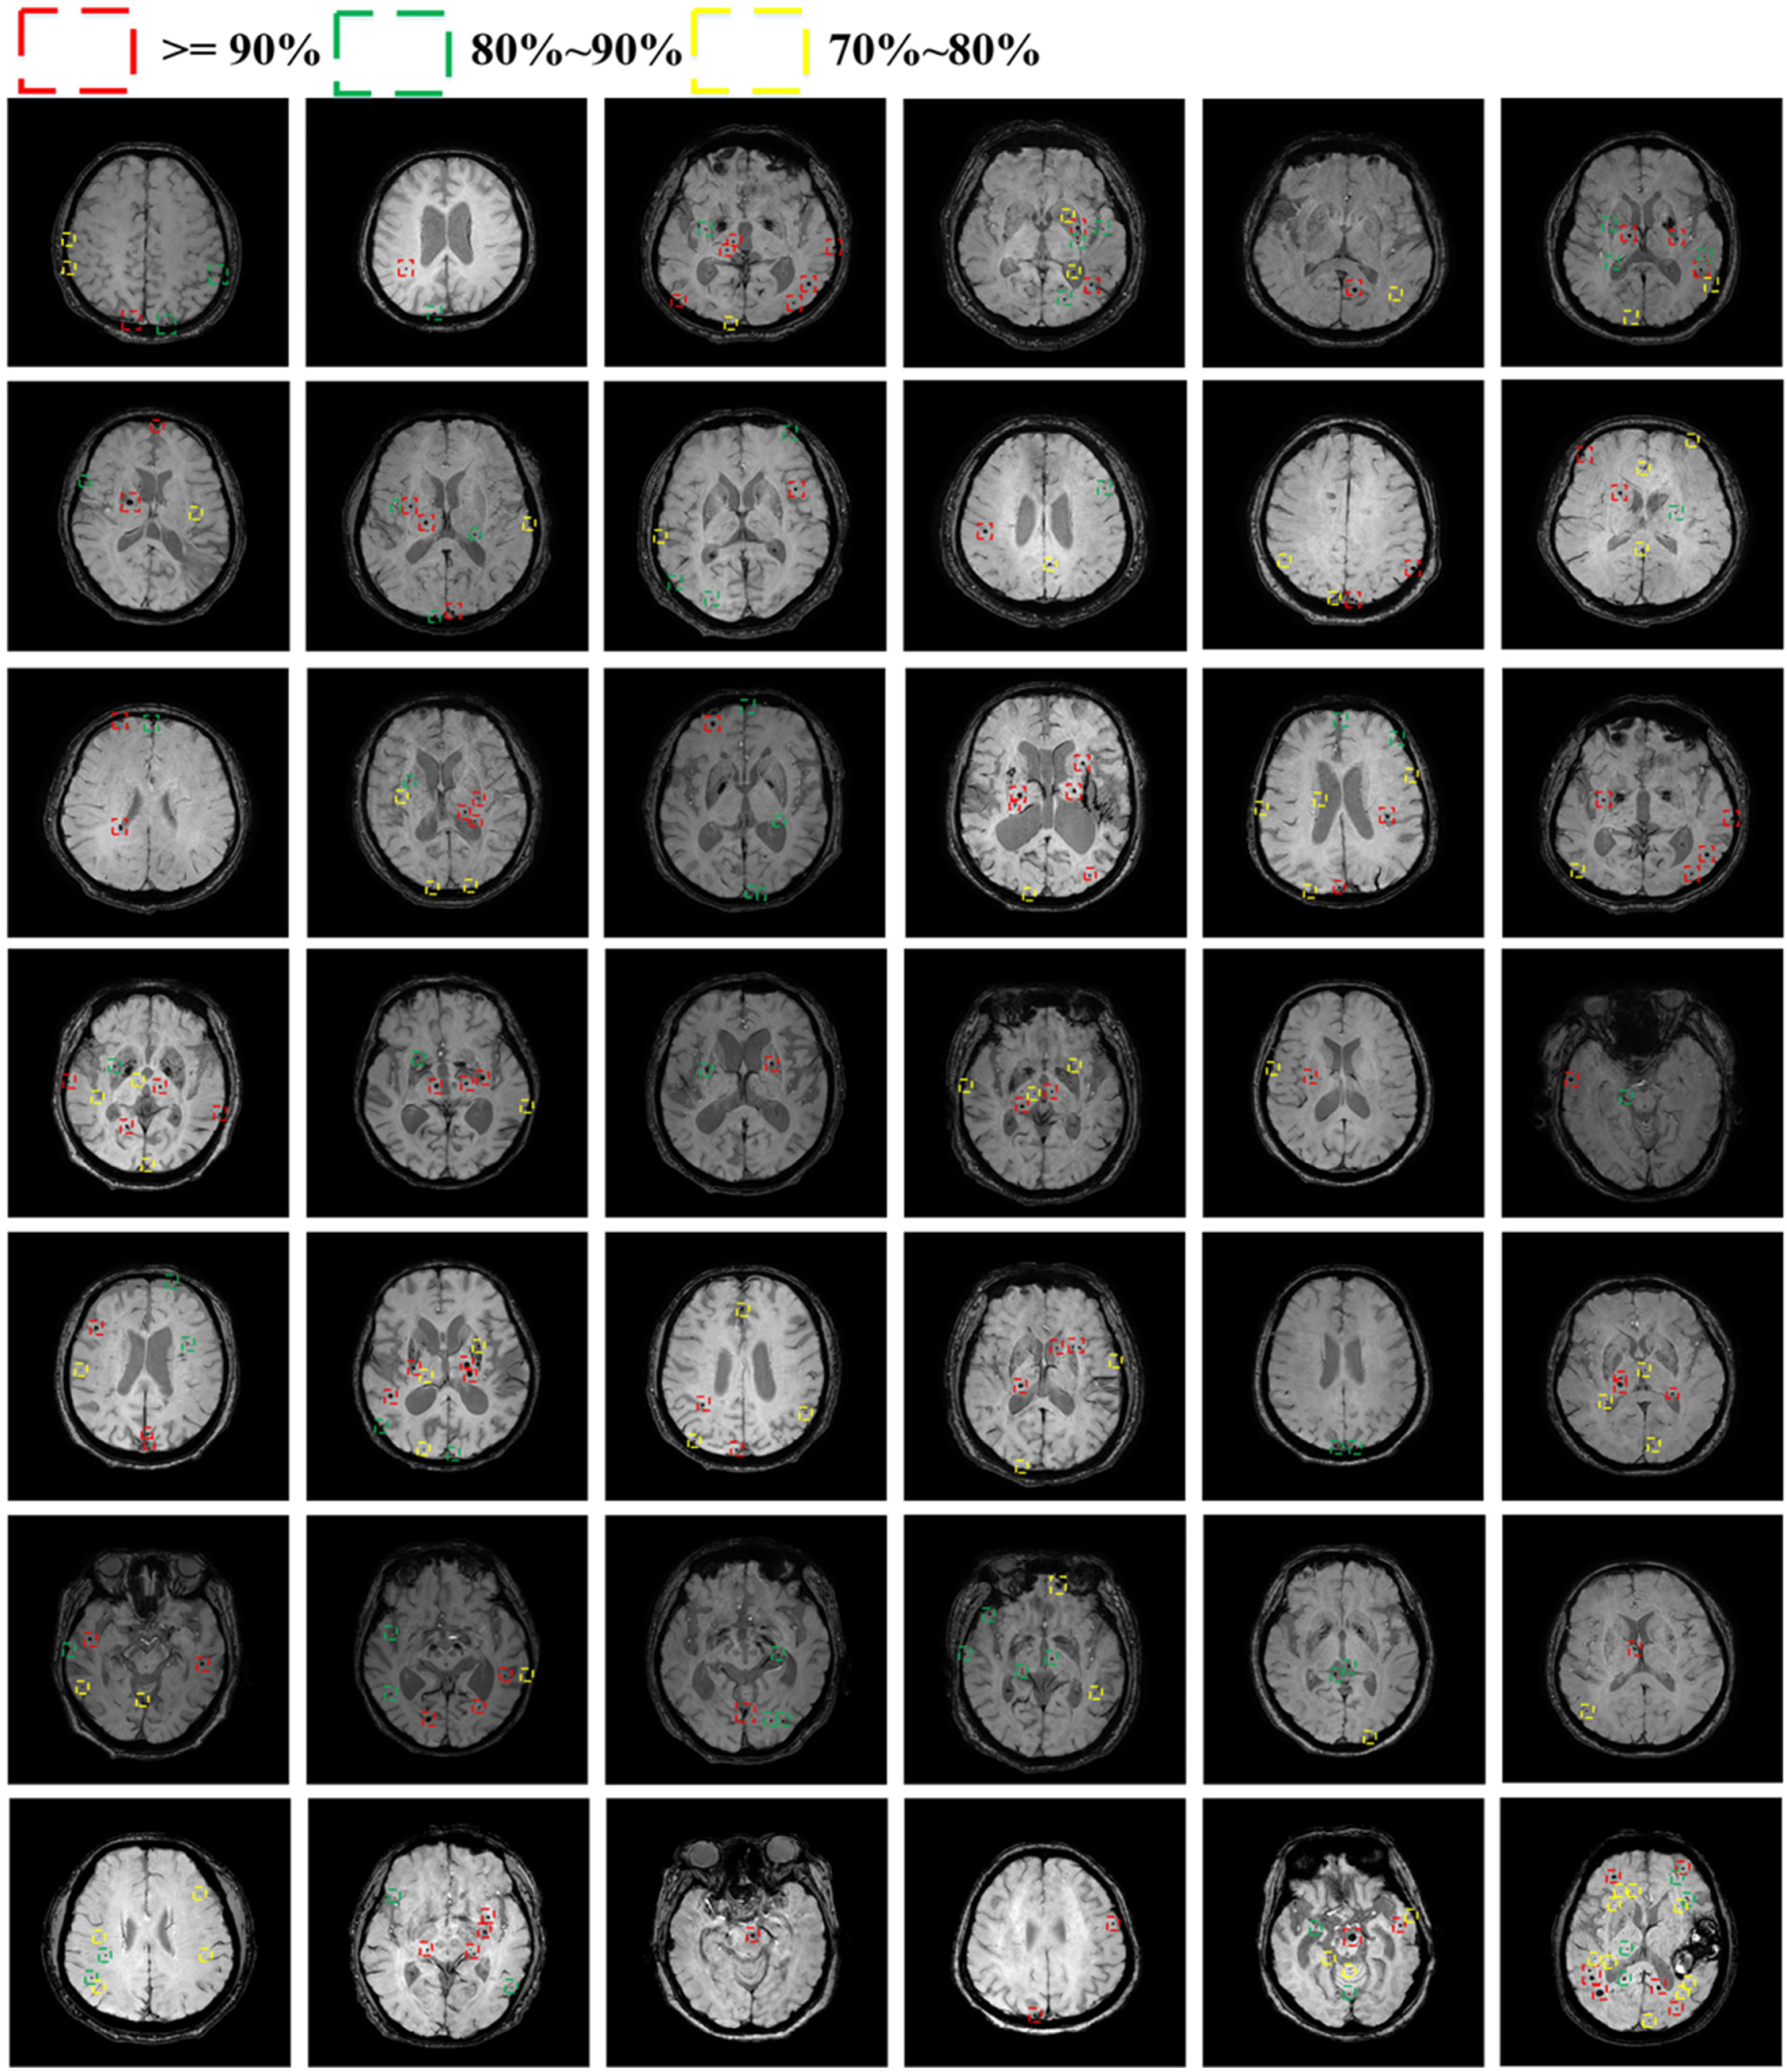

4.3.1. Detection Performance of CMBs

4.3.2. Classification Performance of CMBs

4.3.3. Total Performance of CMBs

5. Ablation Study

5.1. Ablation Study in Detection Stage

5.2. Ablation Study of Different Input Resolutions in Detection Stage